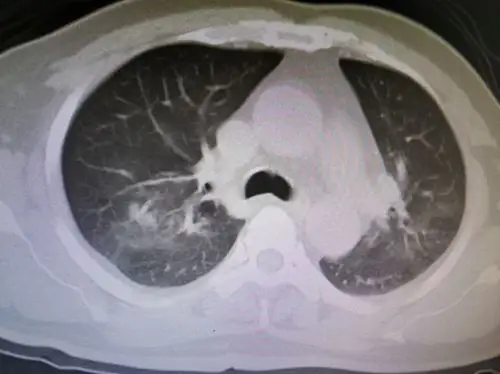

没有任何症状的肺结核